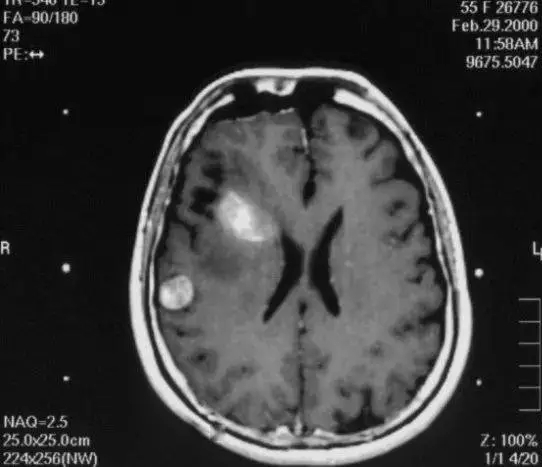

2) 病灶影像定位(MRI或者CT下)

伽马刀又称立体定向伽马射线放射治疗,是融立体定向技术和放射技术于一体,以治疗颅内疾病为主的立体定向放射外科治疗设备。其原理是将钴-60发出的伽马射线几何聚焦,集中射于病灶,一次性致死性的摧毁靶点内的组织,射线经过人体正常组织几乎无伤害,并且剂量锐减,相比其他治疗照射范围与正常组织间界限非常明显,边缘如刀割一样,人们形象称之为“伽玛刀”。